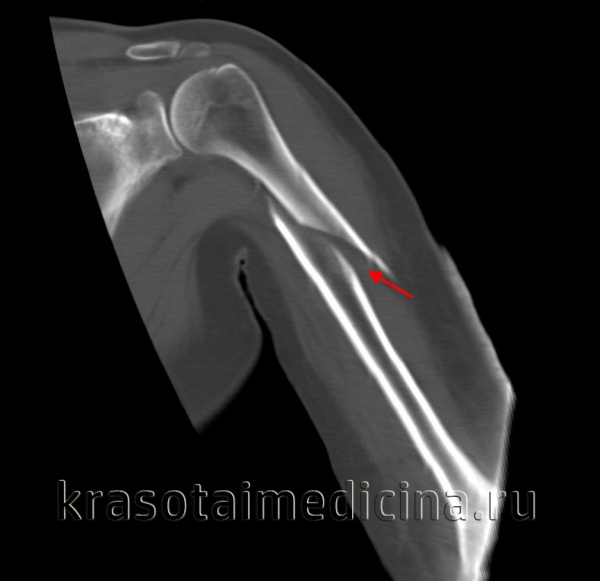

(Слева) На передне-задних рентгенограммах виден пациент, которому планируется лечение по поводу неправильно сросшегося перелома. Через три месяца после перелома (слева) образовалась мозоль, но с варусным 32° и задним 22° отклонением (не показано). Впоследствии было проведено оперативное вправление (справа) с наложением пластины и фиксации шурупами.

(Справа) На задней проекции левой руки близко показан лучевой нерв в диафизе плечевой кости. Среди пациентов с переломами диафиза плечевой кости у 16% наблюдается парез лучевого нерва, проявляющийся свисанием кисти. У большинства наступает улучшение после репозиции смещения и отклонения.